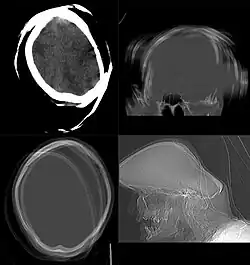

Initially, the CT scanners generated images in only transverse (axial) anatomical plane, perpendicular to the long axis of the body. Modern scanners allow the scan data to be reformatted as images in other planes. Digital geometry processing can generate a three-dimensional image of an object inside the body from a series of two-dimensional radiographic images taken by rotation around a fixed axis.[150] These cross-sectional images are widely used for medical diagnosis and therapy.[151]

Volume rendering

A threshold value of radiodensity is set by the operator (e.g., a level that corresponds to bone). With the help of edge detection image processing algorithms a 3D model can be constructed from the initial data and displayed on screen. Various thresholds can be used to get multiple models, each anatomical component such as muscle, bone and cartilage can be differentiated on the basis of different colours given to them. However, this mode of operation cannot show interior structures.[179]

Surface rendering is limited technique as it displays only the surfaces that meet a particular threshold density, and which are towards the viewer. However, In volume rendering, transparency, colours and shading are used which makes it easy to present a volume in a single image. For example, Pelvic bones could be displayed as semi-transparent, so that, even viewing at an oblique angle one part of the image does not hide another.[180]